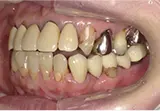

| 年齢/性別 | 70代女性 |

| 主訴 | 左下奥歯に痛みがある、全体的に治したい |

| 治療内容 | 全体的に歯周病やむし歯、根の治療を行い、仮歯を使用して咬合治療を実施。左上、右下、左下の計3本を抜歯し、右上には2本のインプラントを埋入しました。 |

| 治療期間 | 4か月(インプラントのみ) |

| 費用 | 1,116,500円税込 |

| リスク・副作用 | 炎症反応によって術後に腫れや副鼻腔炎が生じることがあります。その程度は、手術の範囲や方法によって異なりますが、多くの場合、時間の経過とともに徐々に治まります。 |